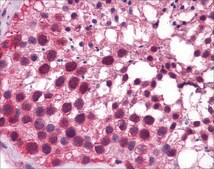

Kruppel-like factor 9 (KLF9) is a transcription factor that regulates several functions such as central nervous systems (CNS) development, villus cell movement, intestinal cell proliferation, and PPARγ-mediated adipocyte differentiation. Furthermore, KLF9 also regulates the differentiation, adhesion and growth of endometrial cells and has been implicated in endometrial carcinoma.

Rabbit Anti-KLF9 antibody is suitable for use in western blot (1.0μg/ml) and IHC (4-8μg/ml) applications.

Krüppel-like factor 9 (KLF9) is a transcriptional regulator of uterine endometrial cell proliferation, adhesion and differentiation; processes essential for pregnancy success and which are subverted during tumorigenesis. The network of endometrial genes controlled by KLF9 is largely unknown. Over-expression of

Krüppel-like factors (KLFs) as a family of zinc-finger transcription factors involve in the regulation of many physiological processes. In these studies, KLF9 was characterized for its role in adipogenesis. The expression of KLF9 was markedly upregulated during the middle stage